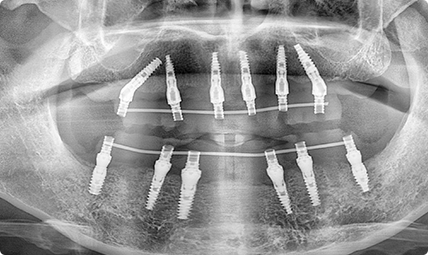

擅长:全口半口种植 种植系统开创者

种即用TM技术

咬啃嚼样样行